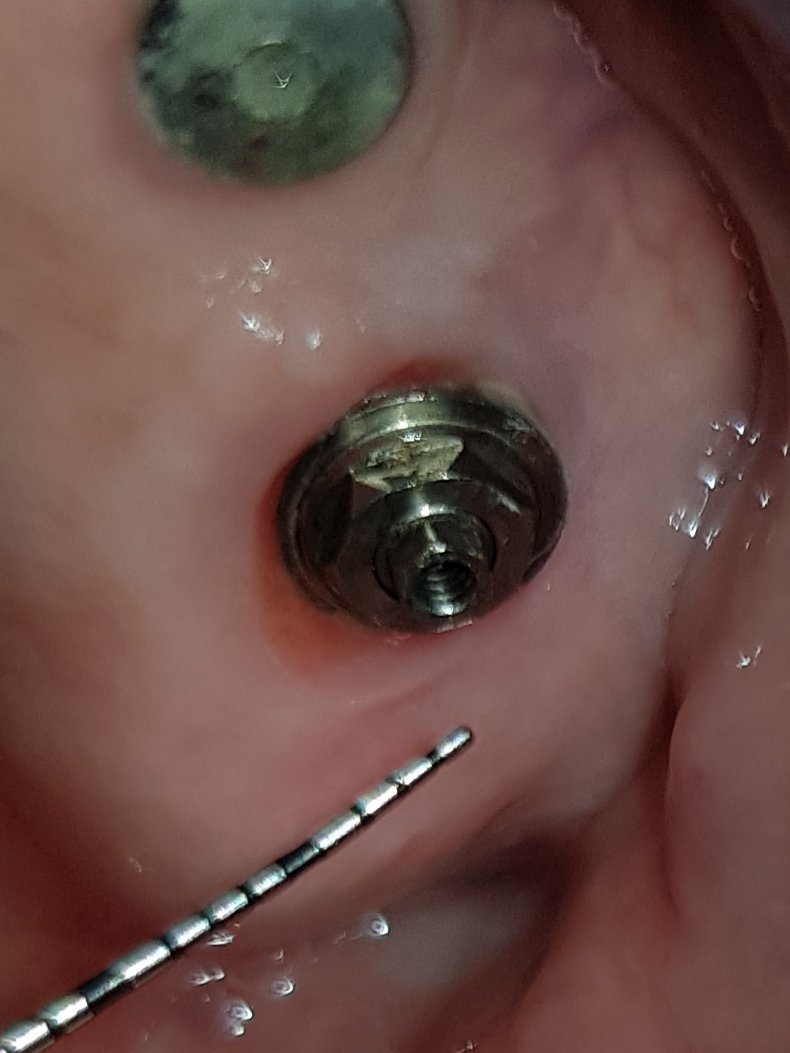

Buenas tardes, Implante colocado en venezuela hace unos 20 años. Muchas gracias de antemano, un saludo

Gracias por vuestra ayuda. Adjunto rx y foto. un saludo.